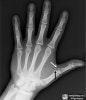

X-ray : 엄지 척측 측부인대 파열(Gamekeeper’s thumb, Skier’s thumb)

골절 혹은 골절-탈구 감별을 위해선 X-ray 검사가 필요합니다.

X-ray상 Bone fragment(골편)이 벌어져 있지 않다면 고정하는 깁스가 필요합니다.

골편이 전이되어 벌어진 공간에 이물로 끼어있다면 수술이 필요합니다.